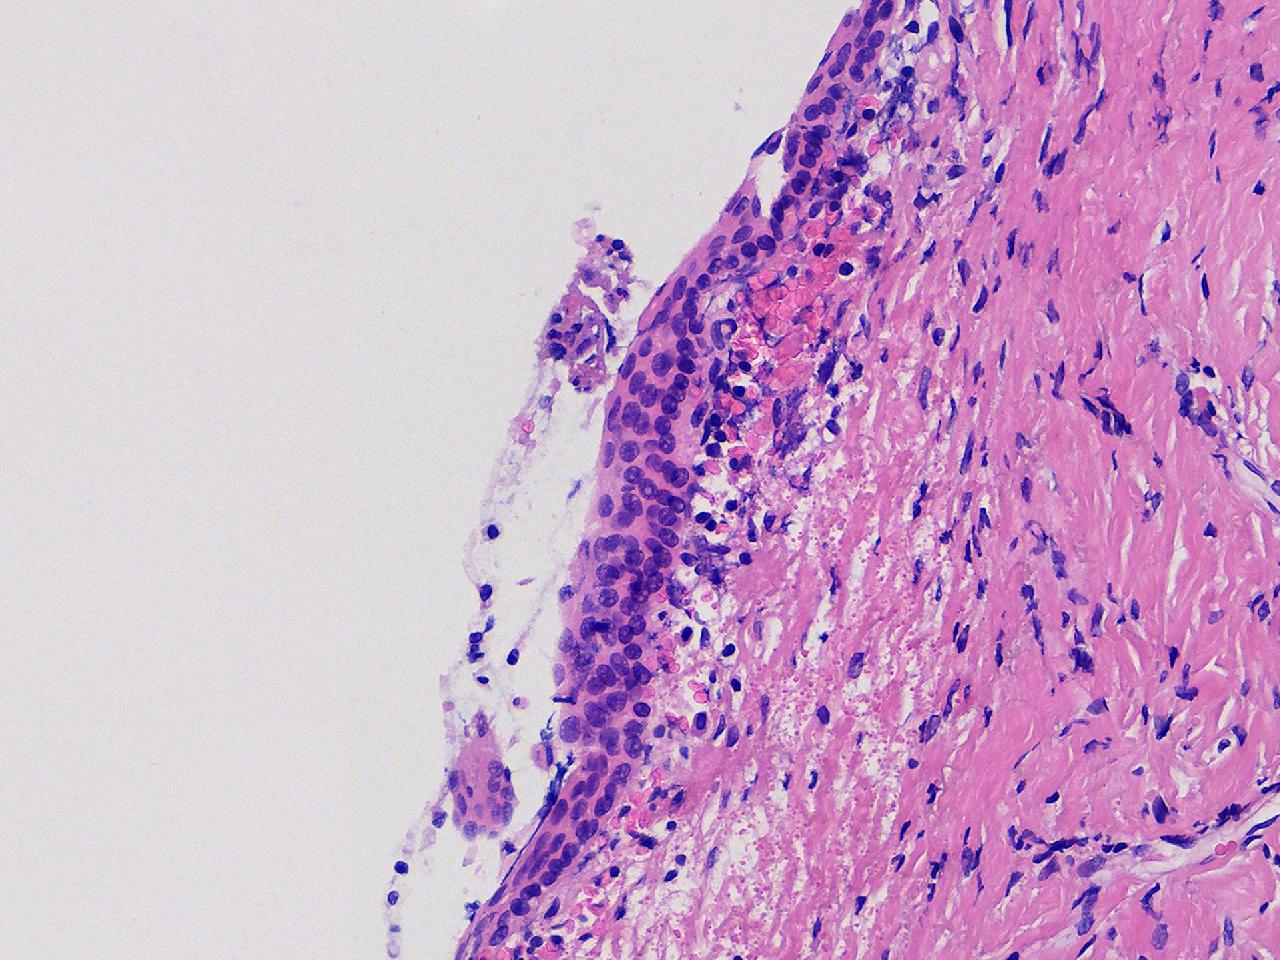

萎缩性? CIN1级?

女,64岁,宫颈活检,HPV不详。

宫颈活检

慢性宫颈炎

萎缩